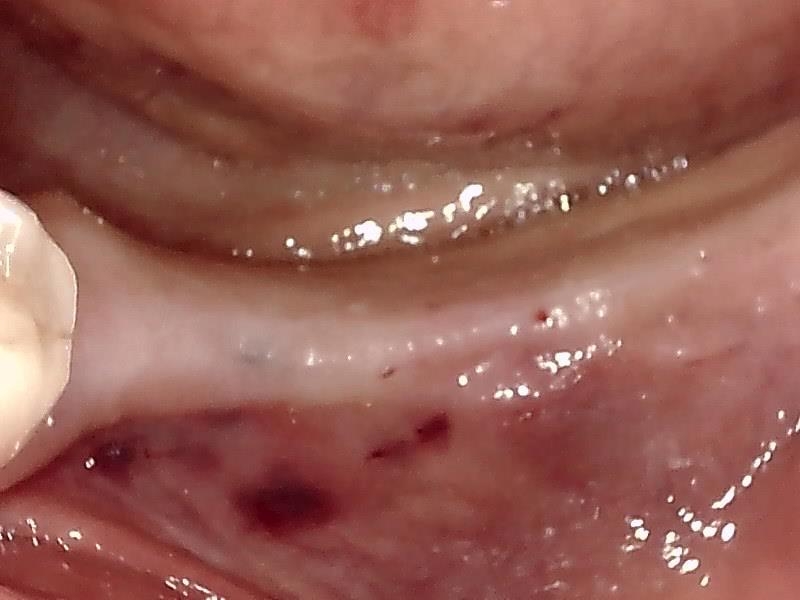

術前の顎堤

顎堤歯肉を減張切開して歯肉剝離する。